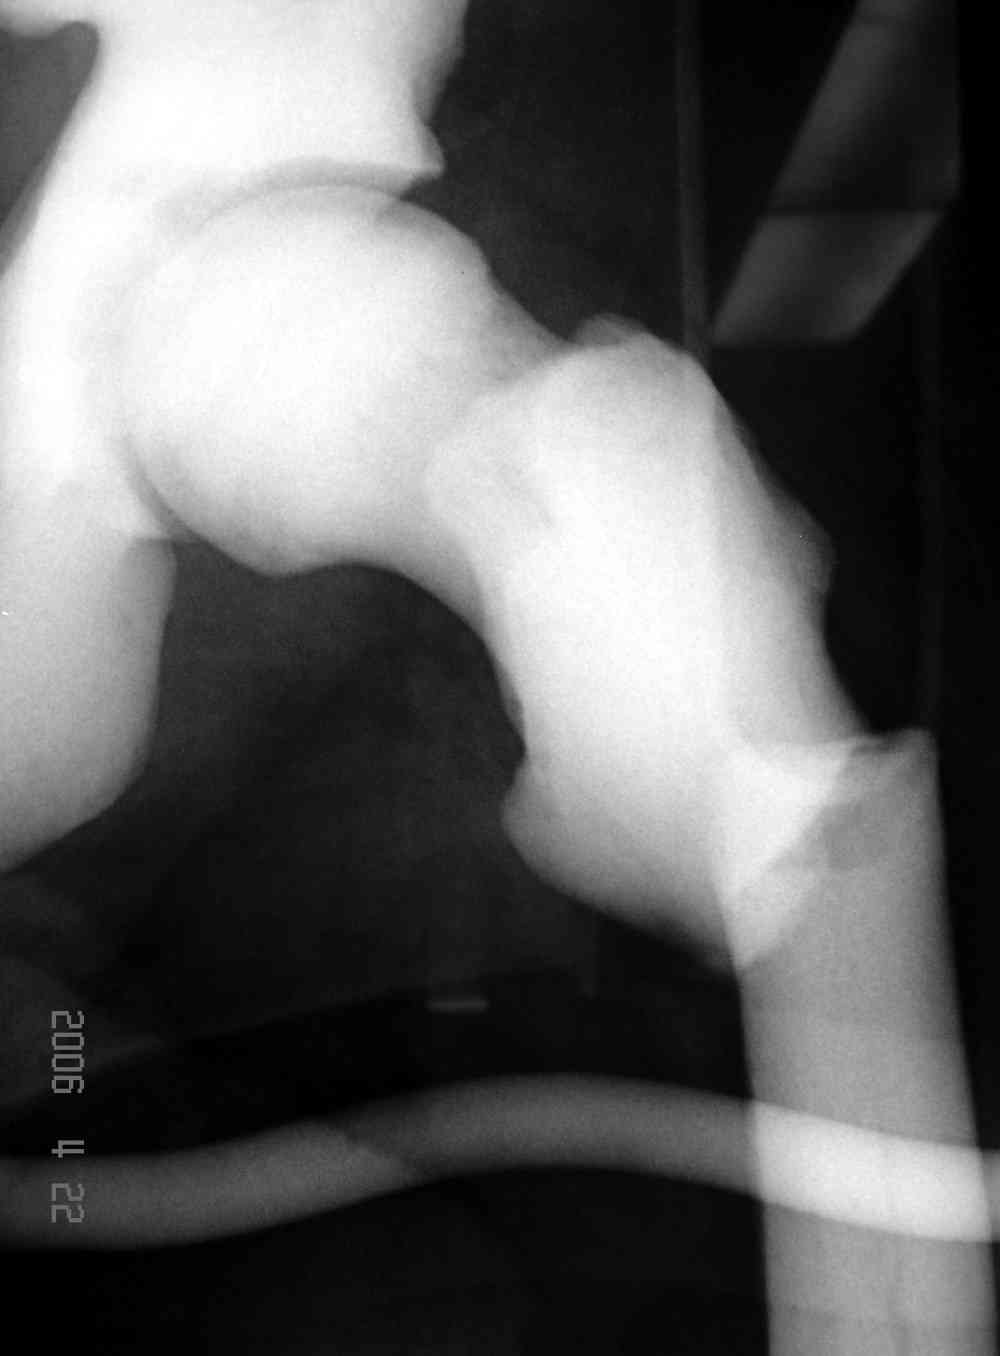

Re: [2/3] Перелом проксимального бедра

Здесь у меня дополнительные снимки с большим разрешением и в разных режимах, а то те дигитал снимки совсем очень блеклые, может, эти изображени изменят выбор тактики